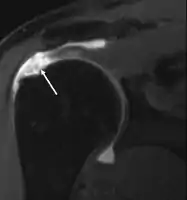

MRI

Magnetic resonance imaging (MRI) and ultrasound[46] are comparable in efficacy and helpful in diagnosis, although both have a false positive rate of 15–20%.[47] MRI can reliably detect most full-thickness tears, although very small pinpoint tears may be missed. In such situations, an MRI combined with an injection of contrast material, an MR-arthrogram, may help to confirm the diagnosis. It should be realized that a normal MRI cannot fully rule out a small tear (a false negative) while partial-thickness tears are not as reliably detected.[48] While MRI is sensitive in identifying tendon degeneration (tendinopathy), it may not reliably distinguish between a degenerative tendon and a partially torn tendon. Again, magnetic resonance arthrography can improve the differentiation.[48] An overall sensitivity of 91% (9% false negative rate) has been reported, indicating that magnetic resonance arthrography is reliable in the detection of partial-thickness rotator cuff tears.[48] However, its routine use is not advised, since it involves entering the joint with a needle, with the potential risk of infection. Consequently, the test is reserved for cases in which the diagnosis remains unclear.

Ultrasound

Musculoskeletal ultrasound has been advocated by experienced practitioners, avoiding the radiation of X-ray and the expense of MRI while demonstrating comparable accuracy to MRI for identifying and measuring the size of full-thickness and partial-thickness rotator cuff tears.[49] This modality can also reveal the presence of other conditions that may mimic rotator cuff tear at clinical examination, including tendinosis, calcific tendinitis, subacromial subdeltoid bursitis, greater tuberosity fracture, and adhesive capsulitis.[50] However, MRI provides more information about adjacent structures in the shoulder, such as the capsule, glenoid labrum muscles, and bone, and these factors should be considered in each case when selecting the appropriate study.